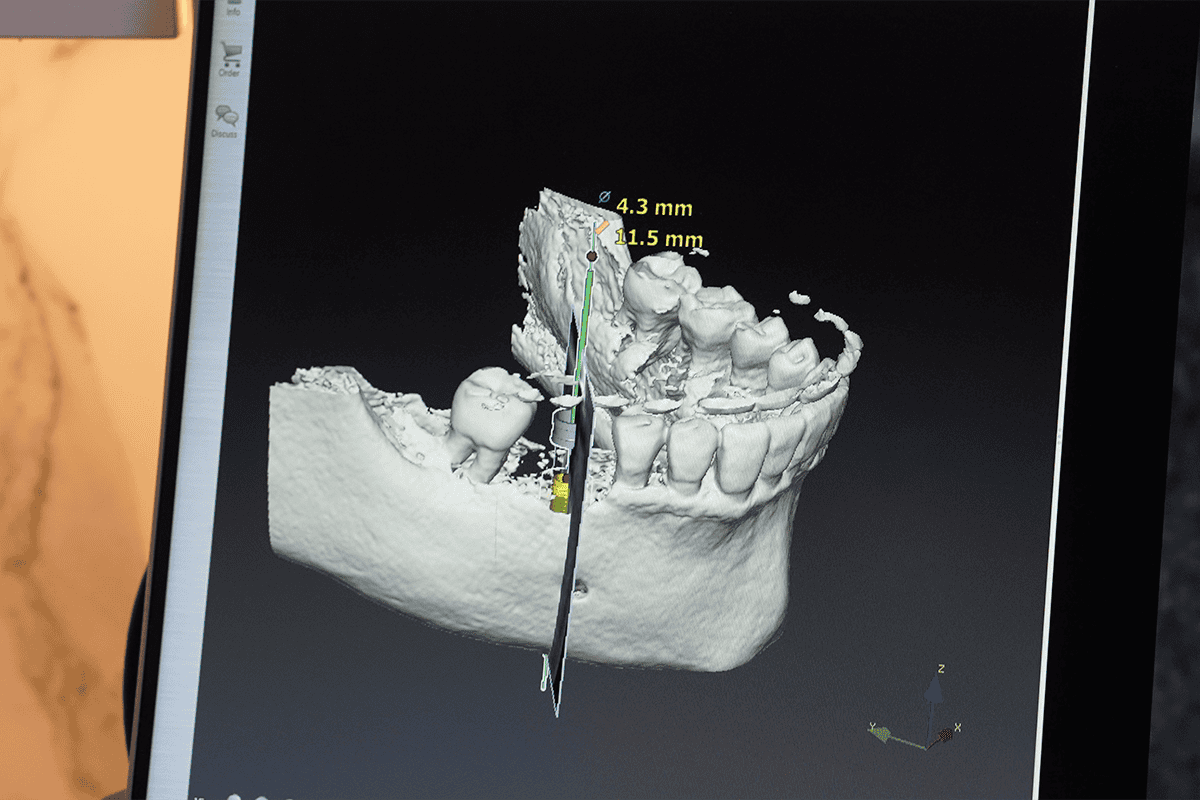

All-on-4 can be an option for people with gum disease, but not in every case. Because periodontal disease affects natural teeth, it is removed when the teeth are extracted during the procedure. However, the extent of damage and the amount of bone available to support implants are key factors. Bone grafting may sometimes be possible if bone loss has occurred, but this is carefully assessed for each person.

At Advanced Dental Artistry, we use detailed scans and thorough examinations to understand your teeth, gums, and bone structure. If needed, we address any underlying oral health issues first to help ensure a strong foundation before moving forward with implants.